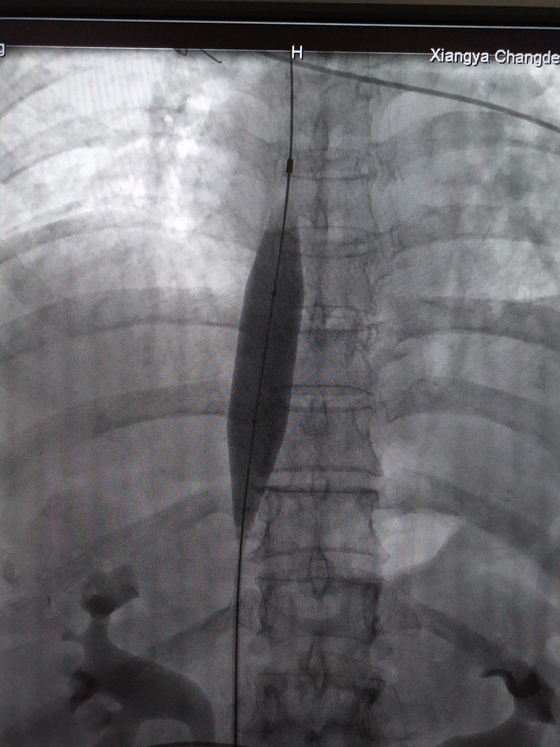

3月25日,在放射介入科主任胡康新教授的指导下,汤金城医师、李毅副主任医师和黄彬副主任医师为患者实施介入治疗。手术在DSA引导下,医生先经股静脉置管进行造影,明确诊断并确定了病变类型,观察下腔静脉的狭窄程度和梗阻远端有无血栓以及肝静脉是否通畅。随后从右颈静脉插入另一导管,经上腔静脉和右心房导入下腔静脉上端,两根导管同时注入造影剂,以便更清楚的了解病变长度。在明确了病情后,医生再经导丝插入球囊扩展导管置狭窄处,经反复扩张后,直至球囊完全张开。扩张后,植入内径合适的“Z”形支架。手术仅历时一个半小时,手术顺利完成,病人安返病房。

支架植入术后

目前,介入治疗是布加综合征的首选治疗方案,相较外科全麻开胸、开腹,介入治疗作为非开放式手术,手术创伤小,安全性高,病人所受痛苦小,还可重复进行。未来,随着介入学科的发展,介入治疗将代替越来越多的外科手术治疗,成为更多临床疾病诊疗的首选方案。